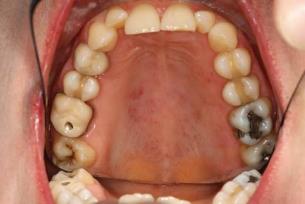

Az arcon szimmetrikusan pillangó formájú erythema látható, mely lehet a felszínből kiemelkedő vagy lapos. Általában az orrhátra terjed, de szabadon hagyja a nasolabialis redőket. Bárhol a bőrön kiterjedt, változó méretű, szarusodó papulák alakulhatnak ki. Jellegzetes lehet a hajhullás és a kopasz foltok (alopecia areata) megjelenése (14.7. ábra). A bőrtünetek fény hatására rosszabbodnak. Az orr és a szájüreg területén hyperkeratotikus, fehér szegéllyel határoltfekélyek jelennek meg a bucca nyálkahártyáján, a palatumon (14.8. ábra). Az ajakpíron is kialakulhat erythemás fekélyekkel és hyperkeratosissal tarkított elváltozás. Kísérhetik Sicca-szindrómára jellemző panaszok.